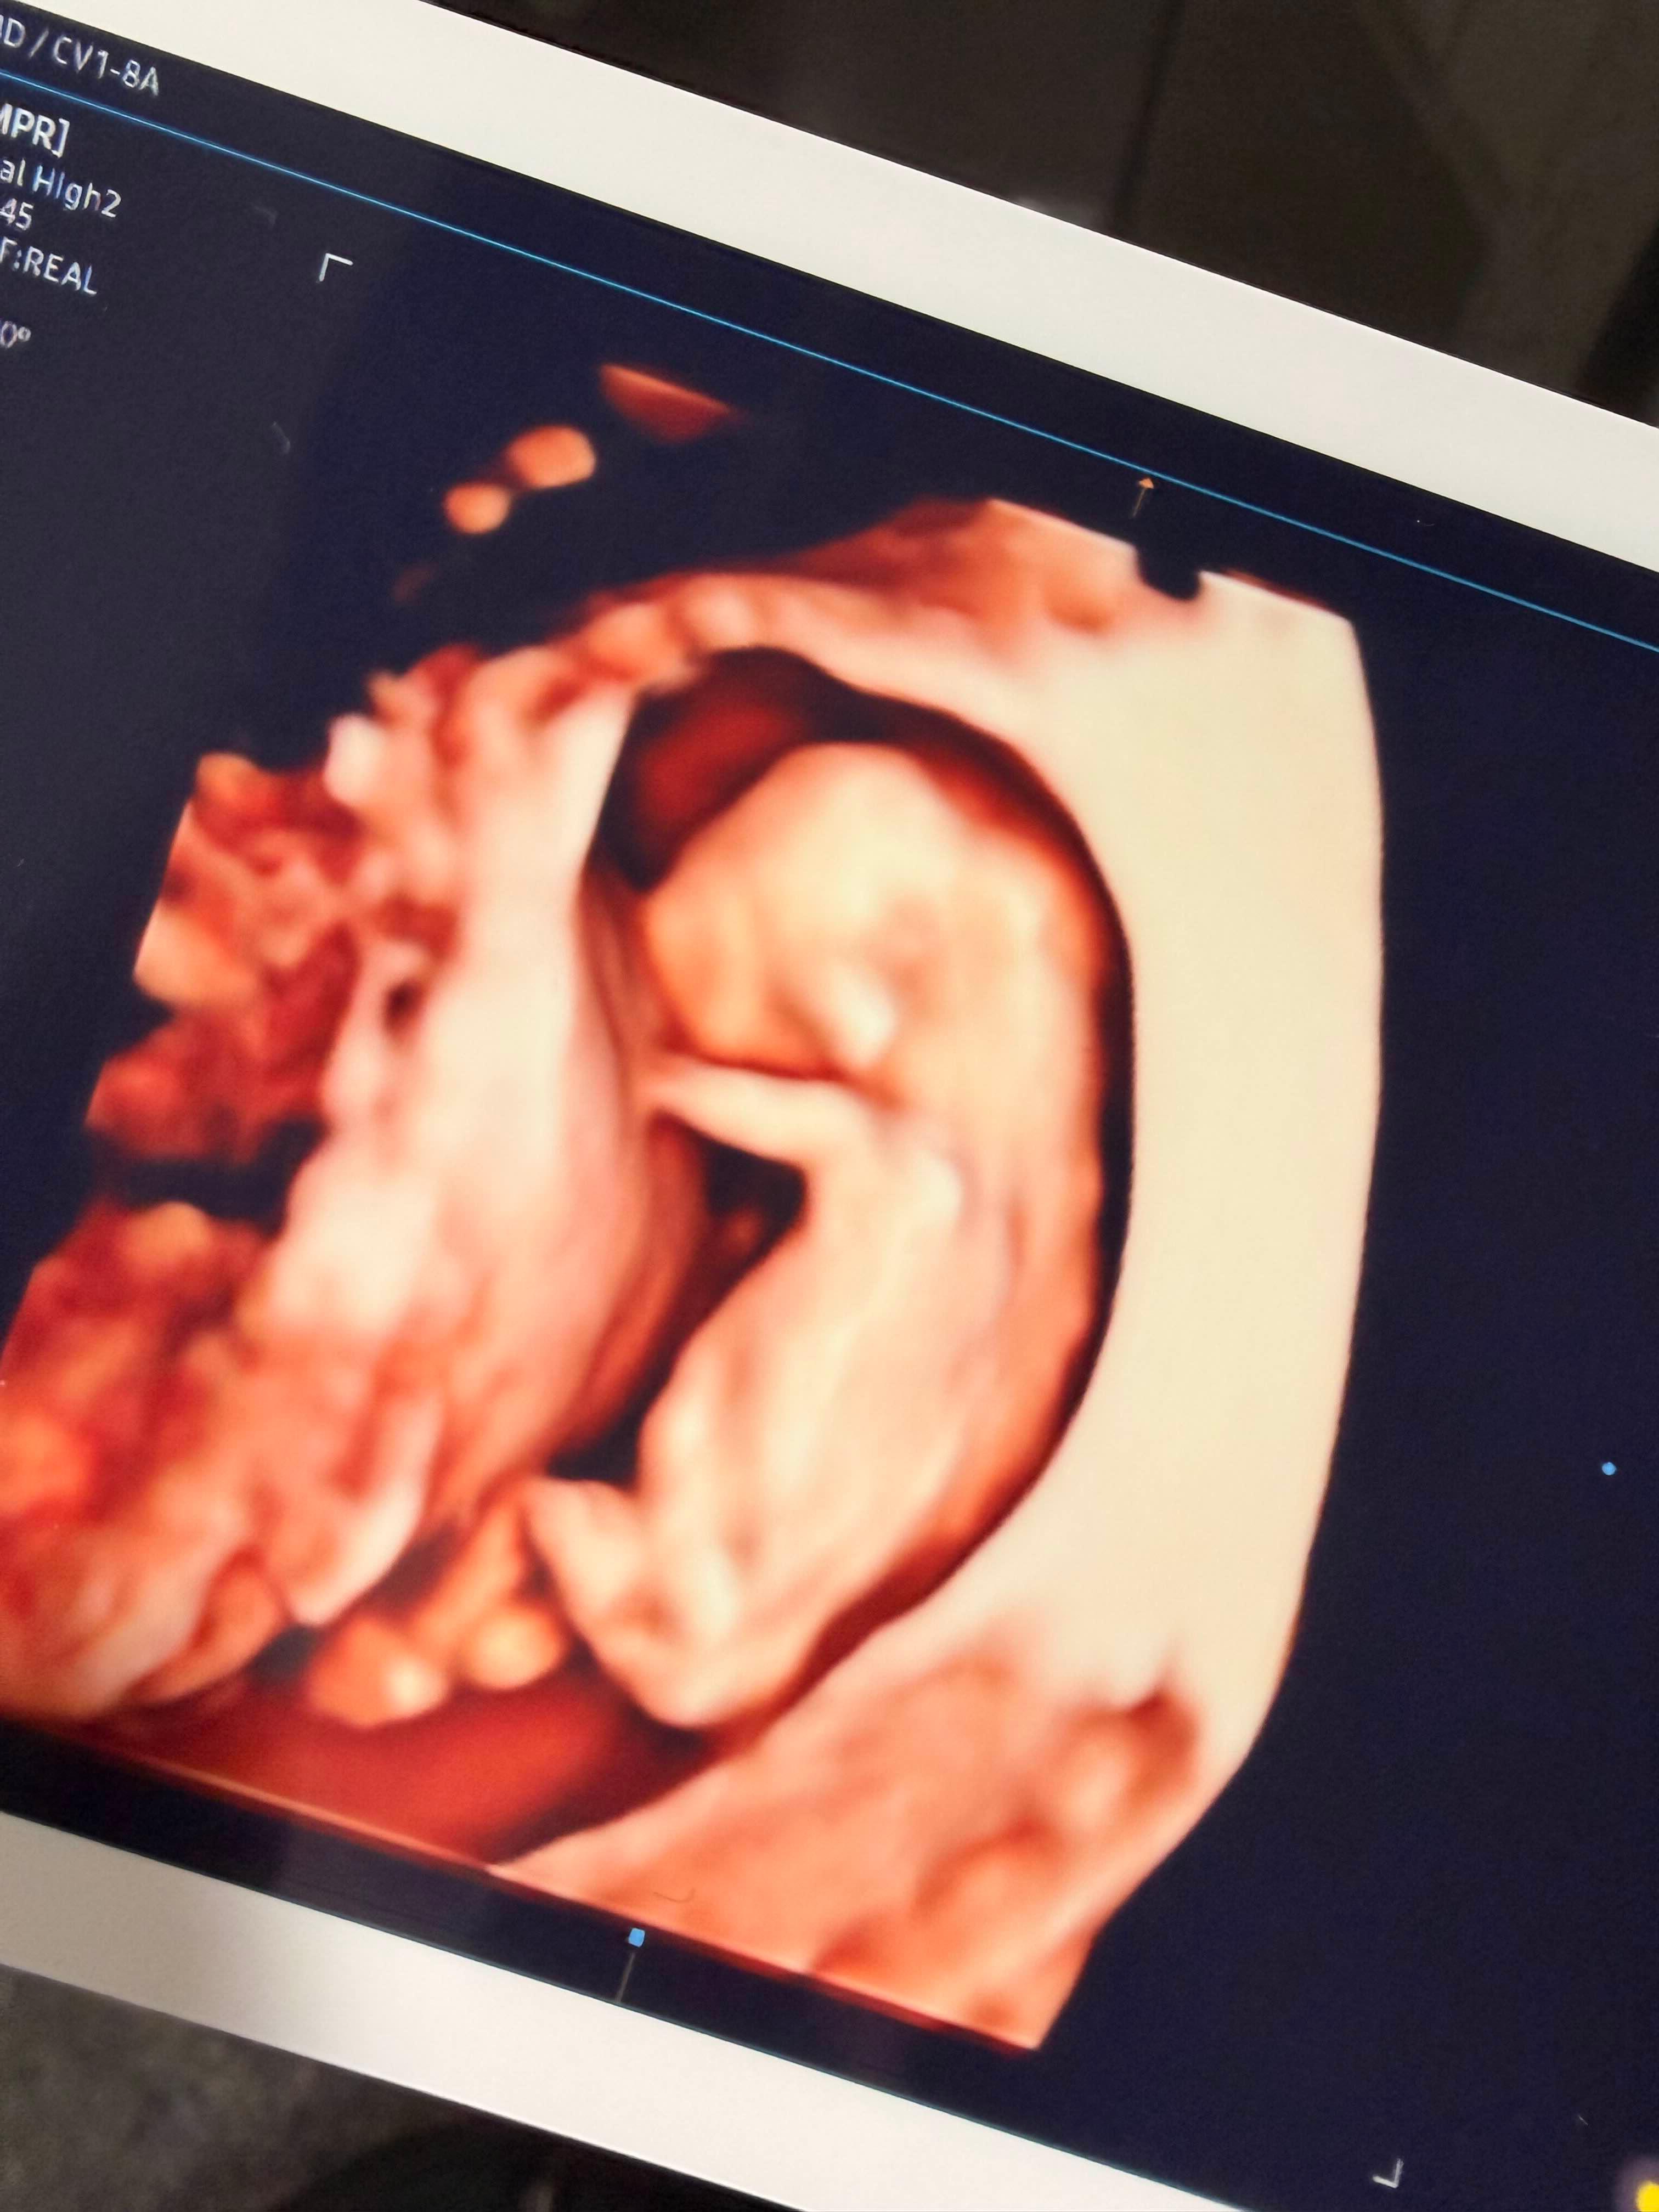

럭키는 3일 전까지만 해도 너무 건강하게 뱃속에서 잘 놀고, 심장도 잘 뛰고, 검사에서도 아무런 이상이 없었다.

그러다 갑자기 원인 모를 이유로 극심한 복통과 출혈과 함께 세상에 너무 빨리 나와 우리 곁을 떠나게 되었다...